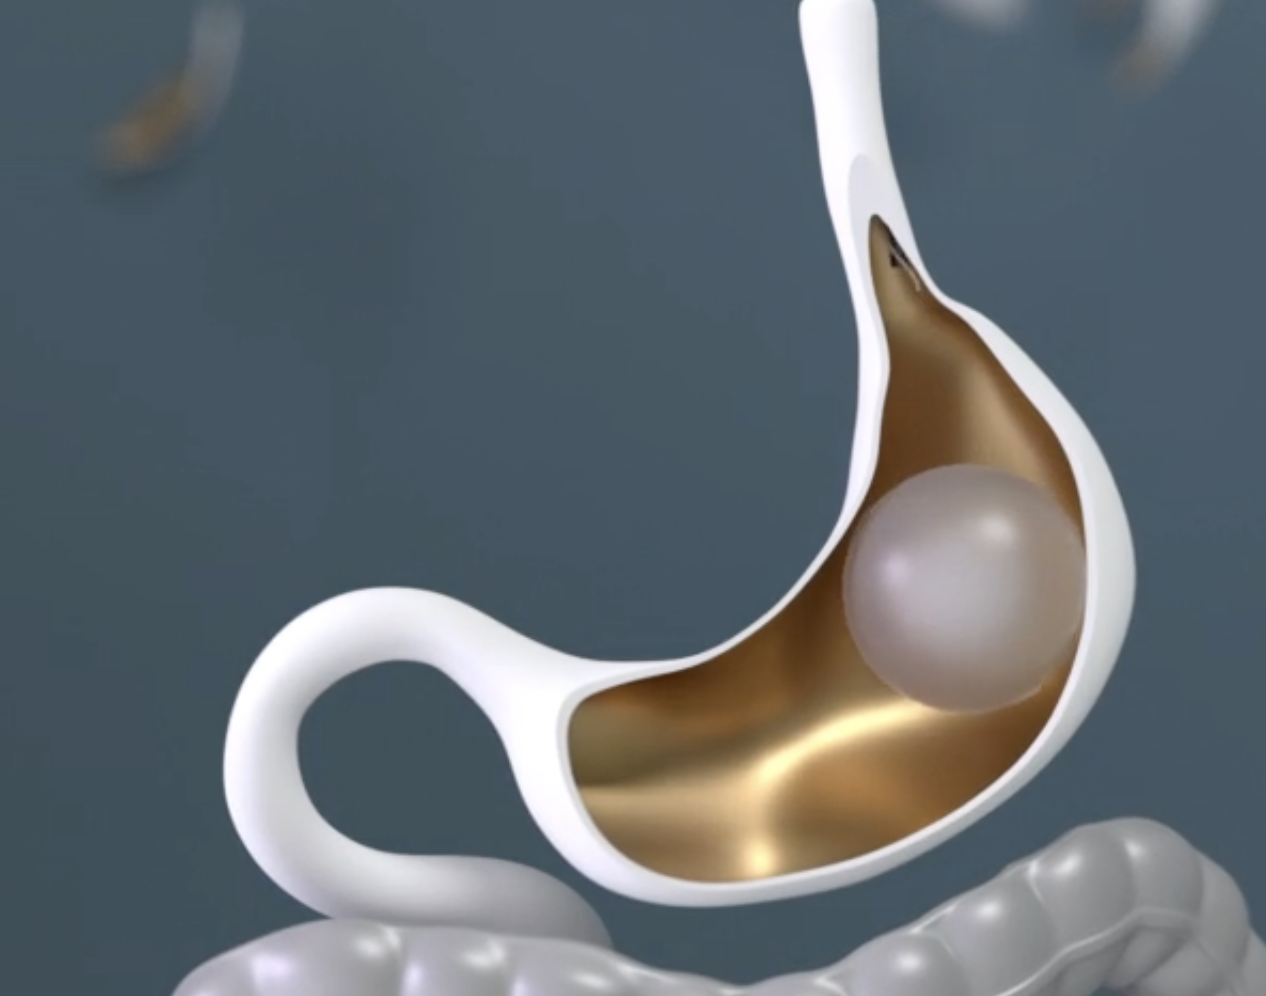

The ESG diet is the structured eating plan patients follow after Endoscopic Sleeve Gastroplasty (ESG). ESG is a noninvasive weight loss procedure that reduces the size of the stomach, allowing patients to eat less while still feeling full and satisfied. But ESG isn’t just a one-time fix—it’s the first step in building a healthier, more confident you.